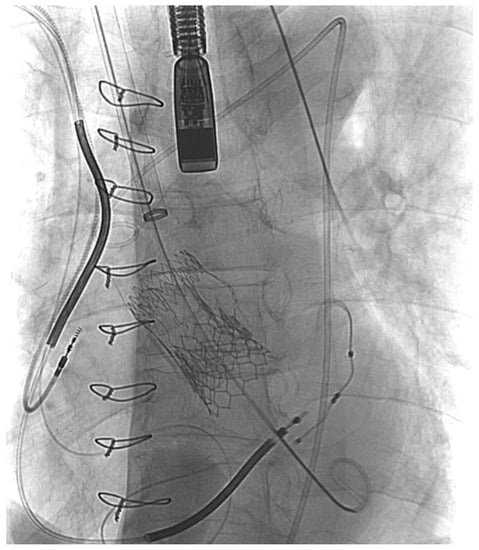

Abdominal Stent-Graft Treatment of Ascending Aortic Pseudoaneurysm Following Transcatheter Aortic Valve Implantation

2. Case Presentation